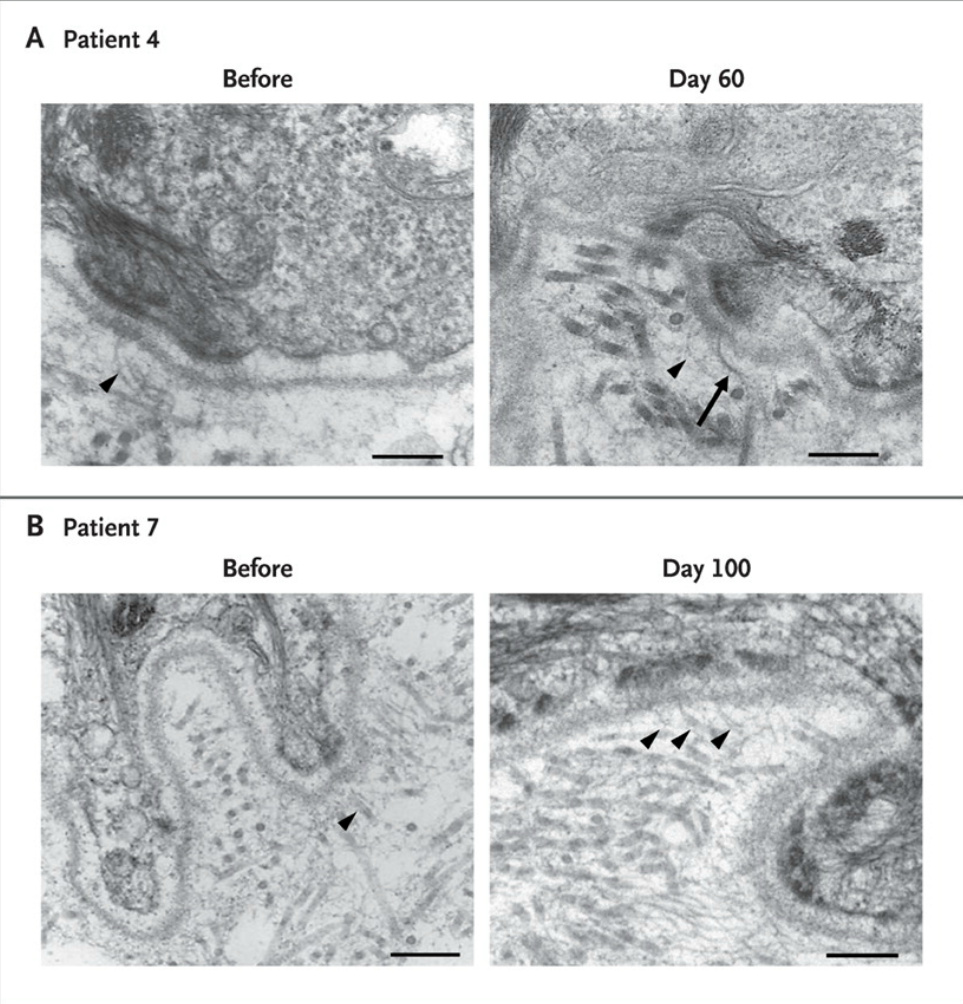

Figure 3. Transmission Electron Micrographs Showing Fibril Formation in Skin Specimens from Patients 4 and 7.

Photomicrographs show thin fibrillar structures beneath the lamina densa before transplantation and on day 60 after transplantation in Patient 4 (Panel A, arrowheads) and before transplantation and on day 100 in Patient 7 (Panel B, arrowheads), with an increase in the number of fibrils after transplantation. Although some of these fibrils appear somewhat thicker in Patient 4 than in Patient 7 (Panel A, arrow), none bear the ultrastructural hallmarks of normal anchoring fibrils. The bars represent 250 nm.